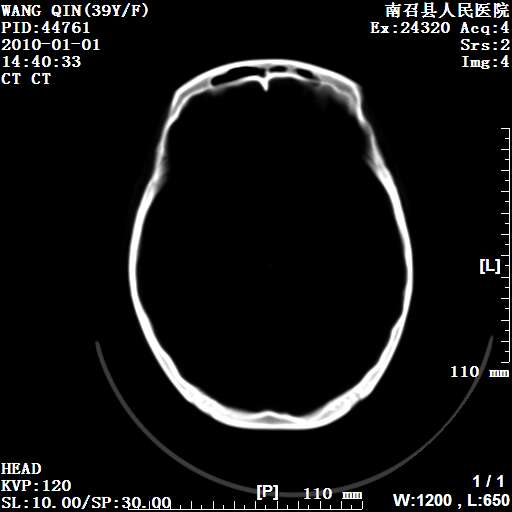

以下是引用随光逐影在2010-1-22 9:03:00的发言:[br]考虑左侧中颅窝(蝶骨翼区)脑膜瘤侵犯蝶骨翼并突入左侧眼眶。

以下是引用水过无痕在2010-1-22 14:55:00的发言:[br]一、定位:颅外占位;二、定性:恶性可能性大;三、组织来源:来源于左侧眼外直肌或其他部位;考虑为:横纹肌肉瘤>转移瘤>脑膜瘤.